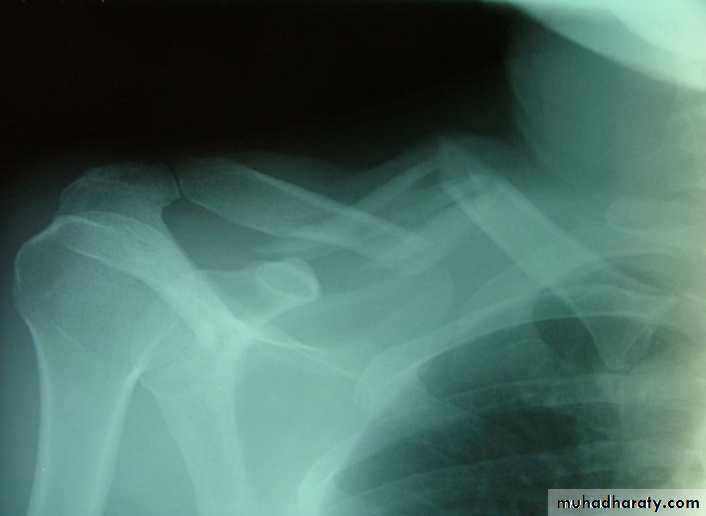

Injuries of the upper limbsFracture clavicle

it is occur due to fall on out stretched hands.The common sites of the fracture in the clavicle is mid shaft .the outer segment displaced down ward and the medial one displaced upward due to the effect of the sternomastoid muscle .

Treatment :by splinting the arm by sling or by use figure of 8 for one month .

accurate reduction is neither possible nor essential .. If there is complication then open reduction and fixation (rarely required)

Figure of 8 in treatment of fracture clavicle